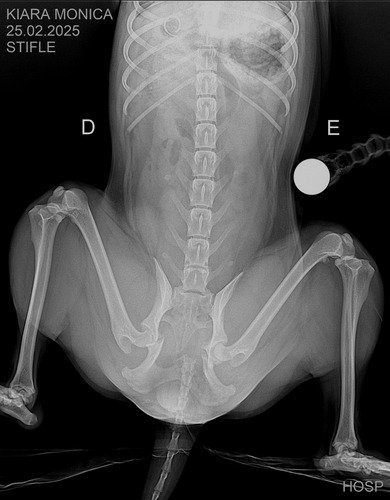

Kiara fez diversos exames e foram constado 3 fraturas, sendo necessário amputação da calda e cirurgia bilateral do quadril